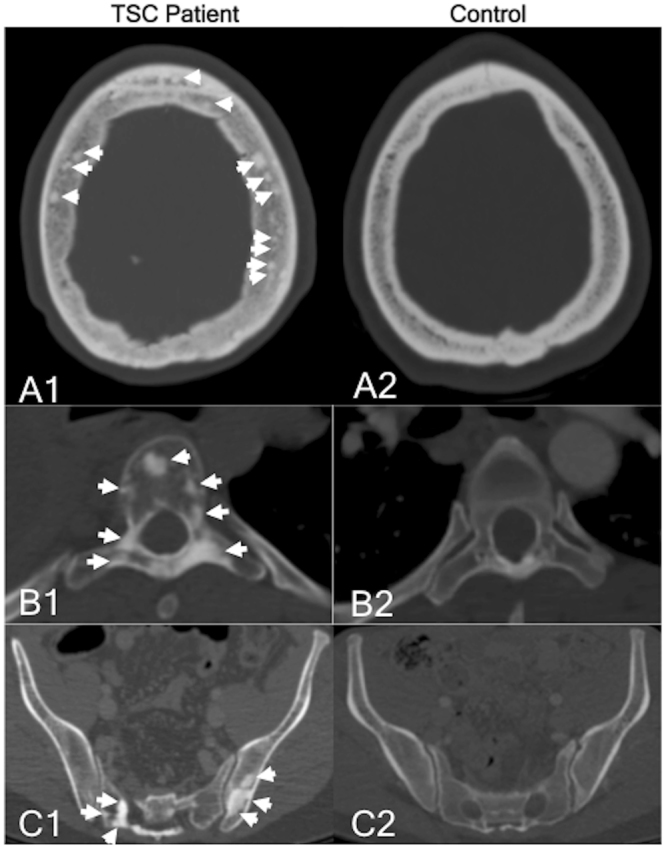

Figure 2.

CT imaging example of the location pattern of sclerotic bone lesions in the skull, spine, and pelvis of TSC patients and control subjects. (A1,A2) Transversal CT of the skull of a TSC patient and a control subject. (A1) A relatively high number of SBLs (indicated by white arrows) can be seen in the spongiosa of the skull. The highest number of SBLs can be found in the os parietale and the os frontale. (A2) Normal spongiosa of a control individual without focal sclerotic bone lesions. (B1,B2) Transversal CT of the spine in a TSC patient and a control subject. (B1) The highest number of SBLs (indicated by white arrows) can be detected in the thoracic spine in the vertebral body and the arcus vertebrae/processus spinosus. Other osseous structures (e.g. sternum or ribs) were also affected, but to a lesser degree. (B2) Normal spongiosa of a control individual without focal sclerotic bone lesions. (C1,C2) Transversal CT of the pelvis in a TSC patient and a control subject. (C1) In the abdomen/pelvis, the second-highest number of SBLs (indicated by white arrows) could be detected in the pelvis. The highest number could be detected in the spine (example please see Fig. 2, B1). Other osseous structures such as the femur were also affected, but to a lesser degree. (C2) Normal spongiosa of a control individual without focal sclerotic bone lesions.